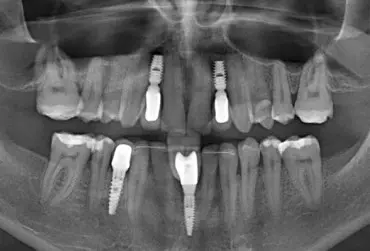

Estetyczna interdyscyplinarna koncepcja leczenia pacjenta z wrodzoną hipodoncją

Choć potrzeba estetycznego uśmiechu była zawsze istotna, w dziejach ludzkości pojęcie estetyki ulegało ewolucji. Obecna była zawsze koncepcja akceptowalnej funkcji w połączeniu z estetyką. Dzisiaj nawet ważniejsza staje się ta druga. Dobry wygląd zębów kojarzy się z sukcesem, szczęściem i pewnością siebie. Z tego powodu jest pożądany. Możliwość nieskrępowanego prezentowania własnego uśmiechu wydaje się urastać do wartości samej w sobie. Zdrowe, piękne, białe zęby są synonimem dobrego statusu społecznego i atrakcyjności.